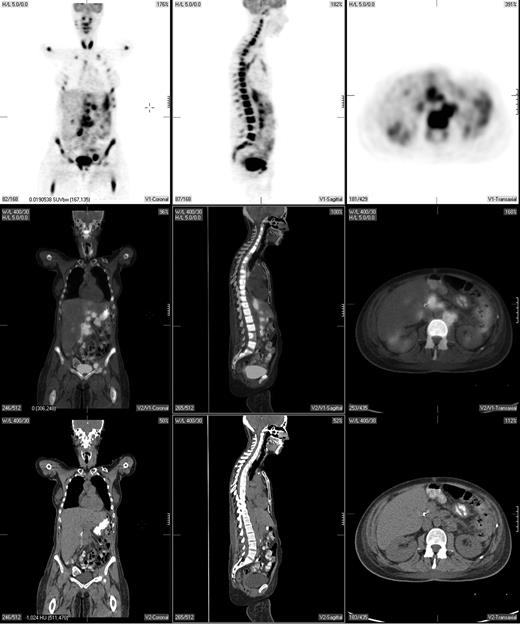

Pretreatment staging determines the extent of disease and helps direct therapy. The Ann Arbor system was initially developed to distinguish patients who might be candidates for radiation therapy from those who would benefit from systemic treatment.29 Traditionally, the Ann Arbor staging system was based on physical examination and bone marrow evaluation but, more recently, CT scans have been incorporated. PET may provide complementary information to conventional staging methods, such as dedicated intravenous contrast-enhanced CT (CECT) and bone marrow biopsy. PET is highly sensitive in detecting nodal and extranodal involvement by most histologic subtypes of lymphoma prior to and following treatment (Figure 1).2,3,20,30-43 Most common types of lymphoma (eg, diffuse large B-cell NHL, follicular NHL, mantle cell NHL, HL) are routinely FDG avid with a sensitivity that exceeds 80% and a specificity of about 90%, which is superior to CT.2,3,33

A pretreatment PET/CT scan in a 48-year-old female patient with Burkitt lymphoma showing widespread nodal and extranodal disease including periaortic, iliac, and mediastinal lymphadenopathy in addition to extensive involvement of the bone/bone marrow, both thyroid lobes and focal liver involvement.

PET and CT are concordant in staging 80% to 90% of patients with diffuse large B-cell lymphoma, follicular lymphoma, and probably also mantle cell lymphoma.33,35 In the 10% to 20% of patients in whom a discordance is observed, PET typically results in upstaging due to the additional presumed sites of disease detected by PET alone such as lymph nodes of 1 cm or smaller in short axis by CT and splenic and hepatic infiltration. In contrast, concordance of PET and CT in determining clinical stage occurs in only about 60% to 80% of patients with HL. Discordant findings occur with a comparable frequency (eg, 10%-20%) in both directions.34,37-42 Although most studies show that PET-negative/CT-positive findings are less common than the converse, it is clear that PET alone cannot replace CT for pretreatment staging of HL.34,37,39,41

PET can detect focal or multifocal bone/bone marrow involvement in lymphoma patients with a negative iliac crest bone marrow biopsy, subsequently confirmed by histopathology or magnetic resonance imaging (MRI)44-46 However, PET alone is unreliable in detecting bone marrow involvement, particularly of limited extent (ie, ≤ 10%-20% of marrow space); estimates of PET sensitivity for detecting marrow infiltration in NHL and HL based on a recently reported meta-analysis were 43% (95% CI, 28-60) and 76% (95% CI, 47-92), respectively.46 While PET may also detect extensive diffuse bone/bone marrow involvement, these patients typically have a positive bone marrow biopsy. Moreover, diffusely increased bone marrow uptake on PET may be due to reactive myeloid hyperplasia, and, therefore, such uptake should be interpreted with caution.45 PET-positive bone/bone marrow findings should be confirmed by biopsy or MRI if a change in treatment is planned based on these findings. Thus, PET cannot substitute for bone marrow biopsy in lymphoma staging.